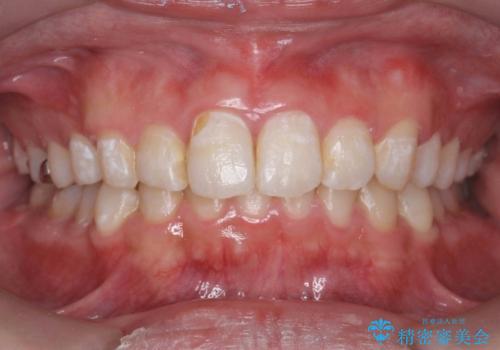

[ 再生治療・歯周外科・小矯正・セラミック補綴 ] 前歯の歯周病治療

担当医 大元洋佑

![[ 再生治療・歯周外科・小矯正・セラミック補綴 ] 前歯の歯周病治療の症例 治療後](https://seimitsushinbi.jp/wp/wp-content/uploads/2022/12/ec16e37ee53325a6f6629b94759f5513-500x350.jpg?v=1671673454)